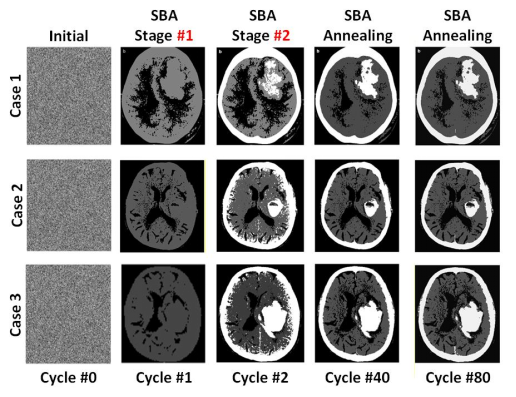

针对以上问题,湖南大学半导体学院陈卓俊教授团队成功设计并流片了一款多态组合优化问题专用处理器。提出了可重构波茨机架构,波茨单元耦合系数复用,以及逐次边界逼近退火技术,大幅提高了解决多态问题的面积效率以及能效。芯片采用65nm CMOS工艺制造,集成256个自旋单元,支持2~4bit的耦合系数位宽,兼容King’s Graph自旋网络拓扑结构,每个自旋的面积仅为4400μm2,并在CT图像聚类、合金相变模拟等应用中完成验证。与同期先进工作相比,该处理器在求解速度、归一化面积等方面达到了最优水平。